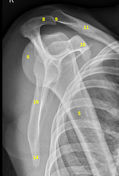

| Grashey | Insufficient obliquity |

| Grashey | Excessive obliquity |

| Grashey | MCP is tilted posteriorly |